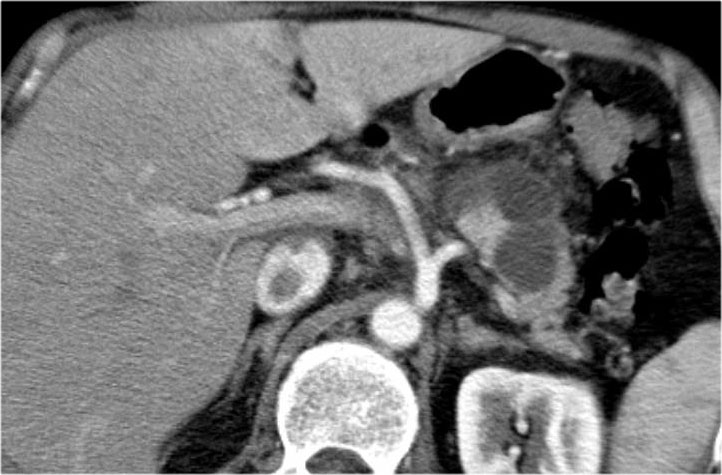

Hình ảnh CT của bệnh nhân nữ 30 tuổi có tiền sử viêm tụy do sỏi mật và đã cắt túi mật.

Bệnh nhân xuất hiện đau bụng trái đột ngột tăng nặng.

Siêu âm cho thấy tổn thương dạng nang tăng kích thước, được chẩn đoán là nang giả tụy (pseudocyst).

Tuy nhiên, CT cho thấy tổn thương dạng nang không có thùy hóa ở đuôi tụy với các vách ngăn bên trong có ngấm thuốc, không thông với ống tụy chính (hình).

Tiếp tục xem hình ảnh MRI…

Chuỗi xung T1W sau tiêm thuốc tương phản từ Gadolinium thể hiện rõ hơn các vách ngăn bên trong.

Phẫu thuật cắt đuôi tụy xác nhận u nang tuyến nhầy kích thước 14 cm có mô đệm buồng trứng (ovarian stroma).